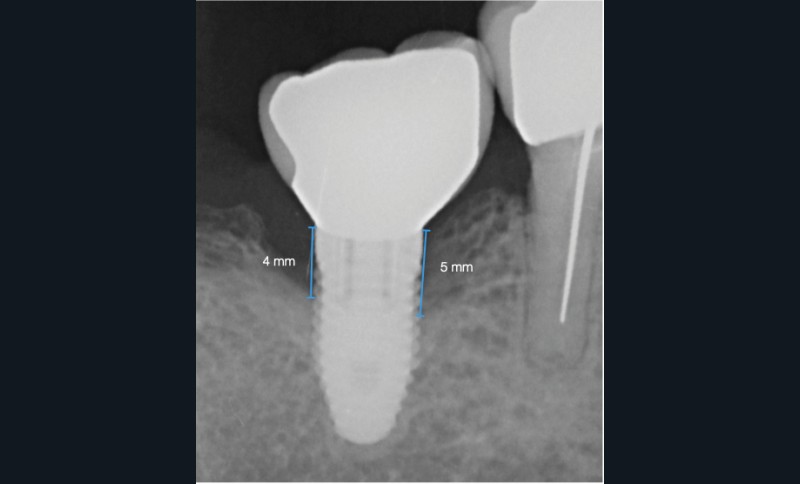

- Péri-implantite sur l’implant 47, diagnostiquée en août 2022

- Poches de 6 à 7 mm

- Nobel Replace Select RP (4,1 x 10 mm)